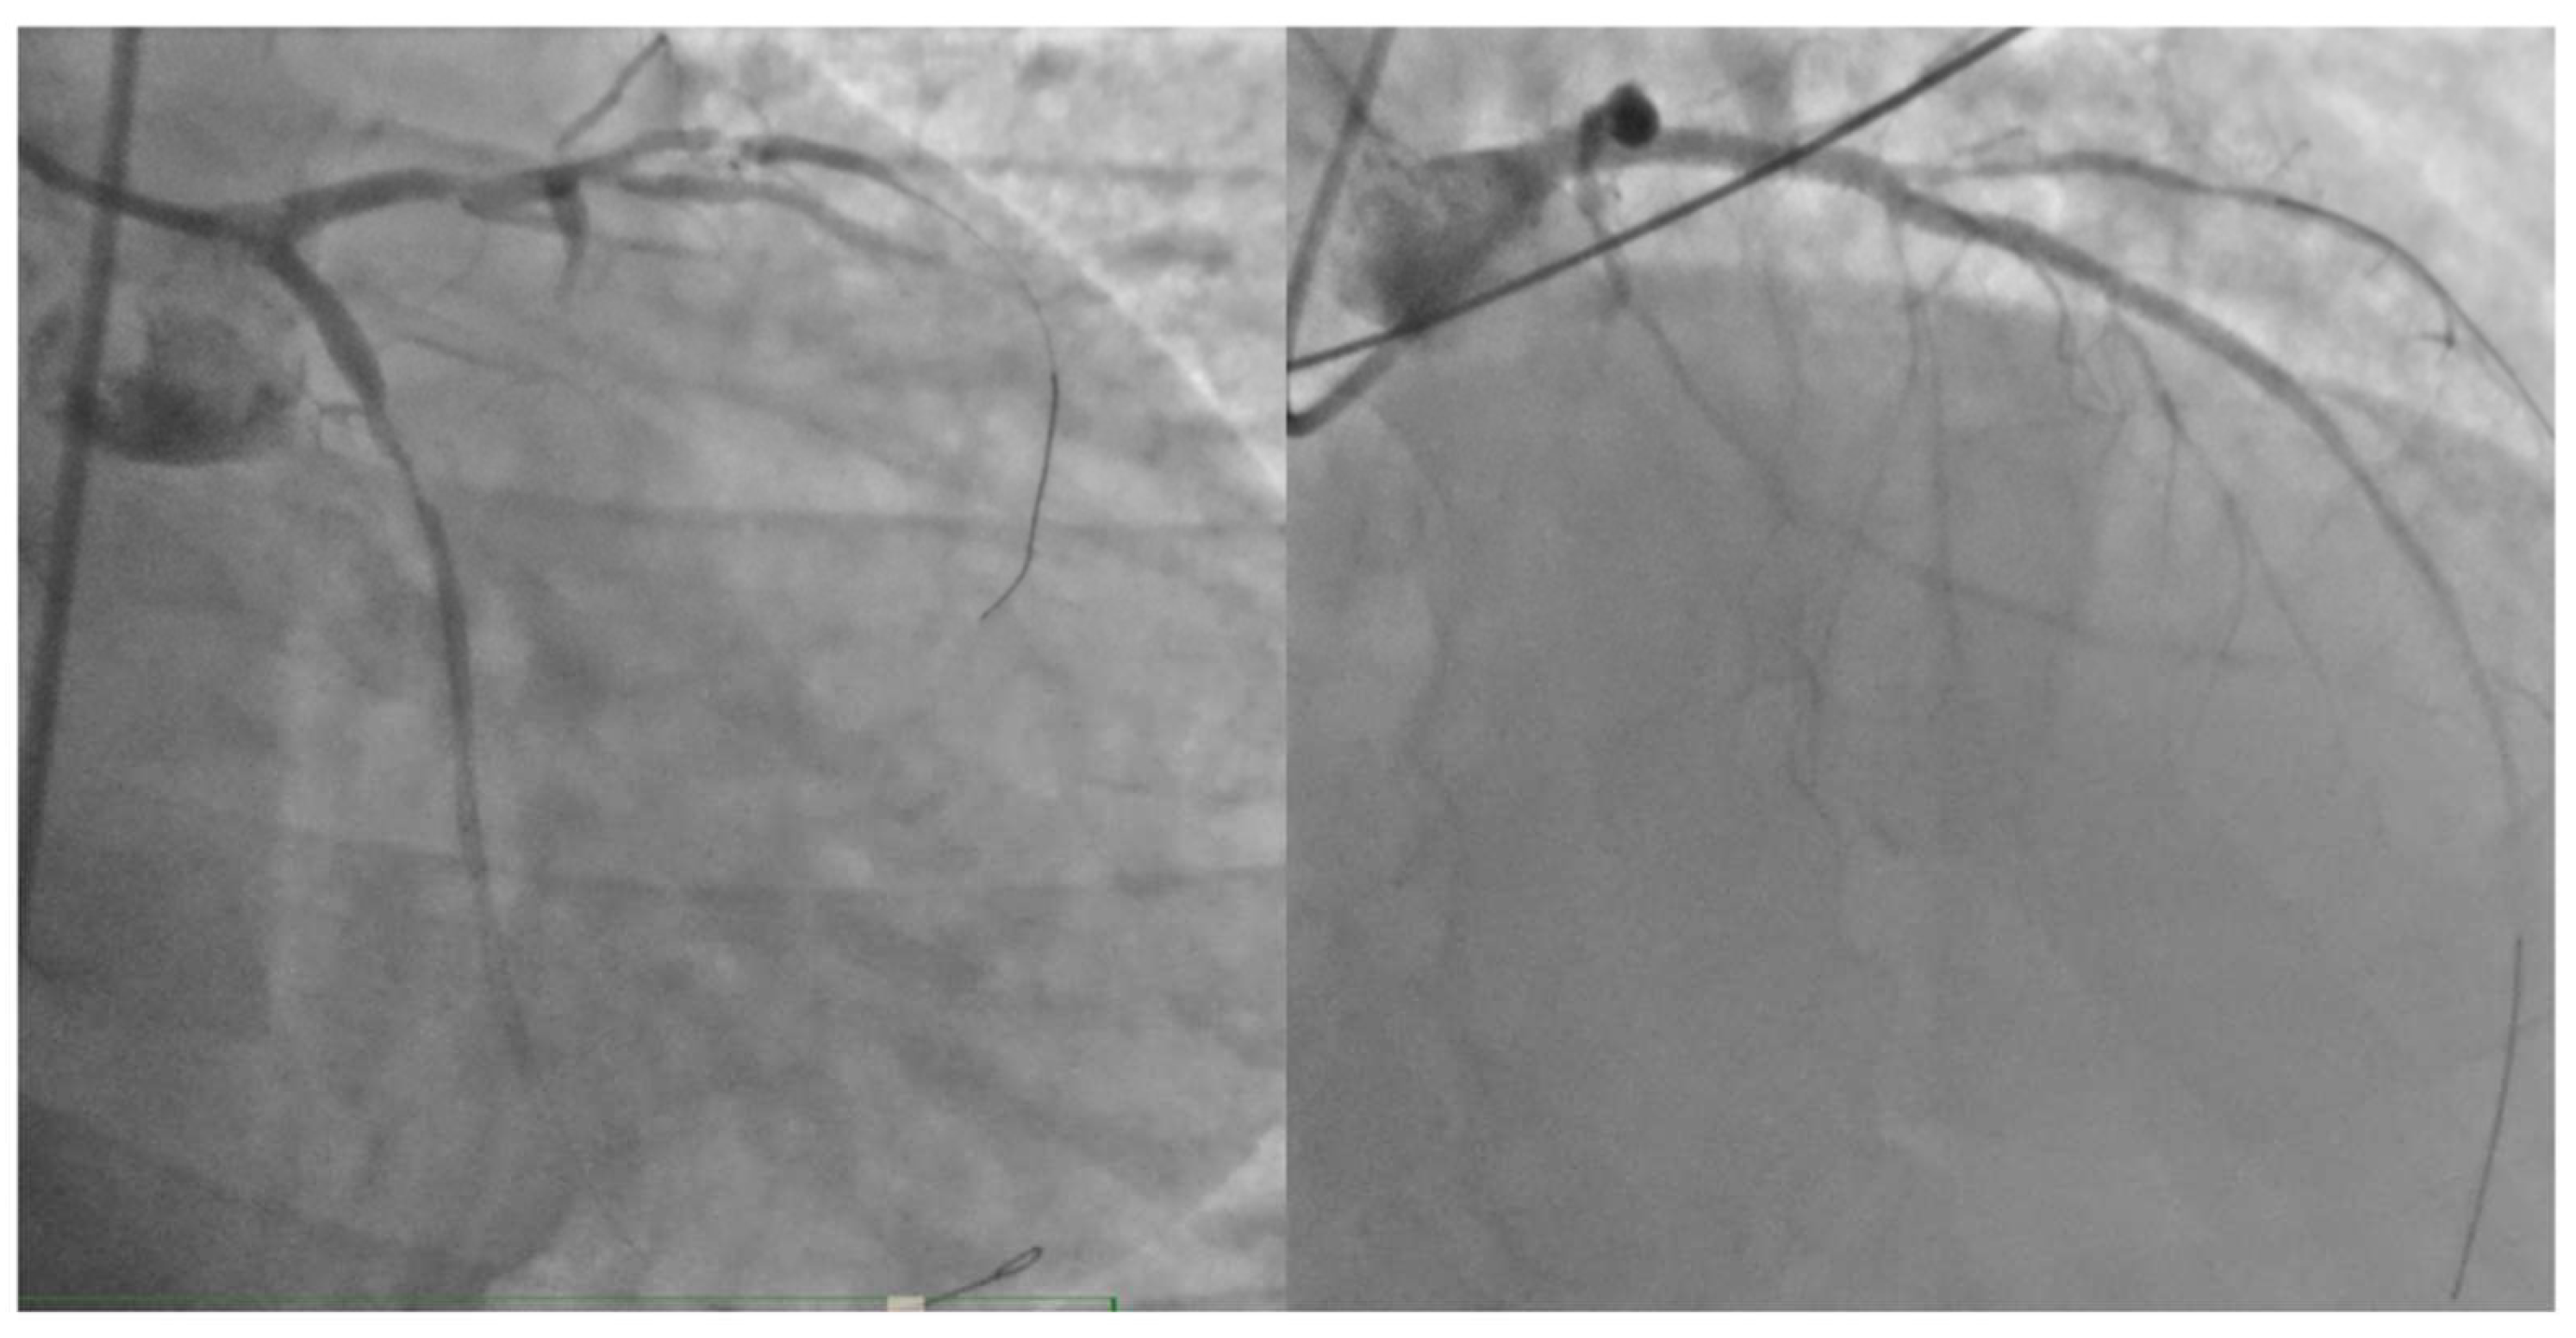

Figure 2. The coronary angiography: Panel A shows the double thrombosis of the left coronary artery at the proximal level of the LAD and the CFX with a TIMI 0 in both vessels; in Panel B, the morphology of the right coronary artery is visible, displaying widespread atheromatous wall changes.

In response to the cardiogenic shock which led to severe hypotension, inotropic therapy with norepinephrine and dobutamine was initiated. The patient was then transferred to the catheterization lab, where acute subocclusion of the proximal circumflex branch and proximal left anterior descending artery (LAD) was identified. Mechanical thrombus aspiration was performed through dual femoral access, and stents were placed in the proximal circumflex branch and proximal LAD. The distal LAD was treated with plain old balloon angioplasty (POBA). An intra-aortic balloon pump (IAPB) was also inserted to support hemodynamics. After the coronary angioplasty procedure, the patient was placed on dual antiplatelet therapy (DAPT) with acetylsalicylic acid and prasugrel. The final result was not optimal, but the vessels were open, as demonstrated in Figure 3.​The peak troponin value was 180,900 ng/L (reference range: 2.5-53 ng/L).

Moreover, compared with the two discussed previous patients, our patient, to our knowledge the first reported case, had a TIMI 0 flow on both the proximal LAD immediately after the left main trunk and on the proximal circumflex before the emergence of any marginal branch. This scenario was equivalent to a TIMI 0 flow at the level of the left main trunk; indeed, the ECG was quite typical of a left main trunk involvement with strongly positive AVR, despite the presence of a right bundle branch block.